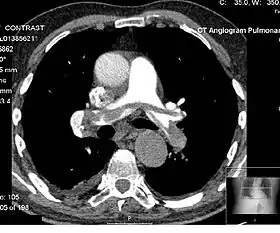

Angiography

Computed tomography angiography (CTA) is a type of contrast CT to visualize the arteries and veins throughout the body.[47] This ranges from arteries serving the brain to those bringing blood to the lungs, kidneys, arms and legs. An example of this type of exam is CT pulmonary angiogram (CTPA) used to diagnose pulmonary embolism (PE). It employs computed tomography and an iodine-based contrast agent to obtain an image of the pulmonary arteries.[48][49][50]